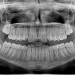

If you fall under the right qualifications of sleep apnea, one of the specialist treatments that can be recommended is through an oral professional or dentist. Your dentists will address your sleep apnea most likely through a device-specific to you. They can assist you by creating a device to help with your problems. Dentists will develop a sort of mouthguard that adjusts or positions your jaw in a way to properly posture your jaw in a way that creates more open airways. This will assist you in sleeping better by being able to breathe throughout the night without interruptions to your sleep. If the problems persist or are worse than a guard can assist with, you might then be recommended for a CPAP machine. This blows air down the throat in order to keep your airways open at night while you sleep.